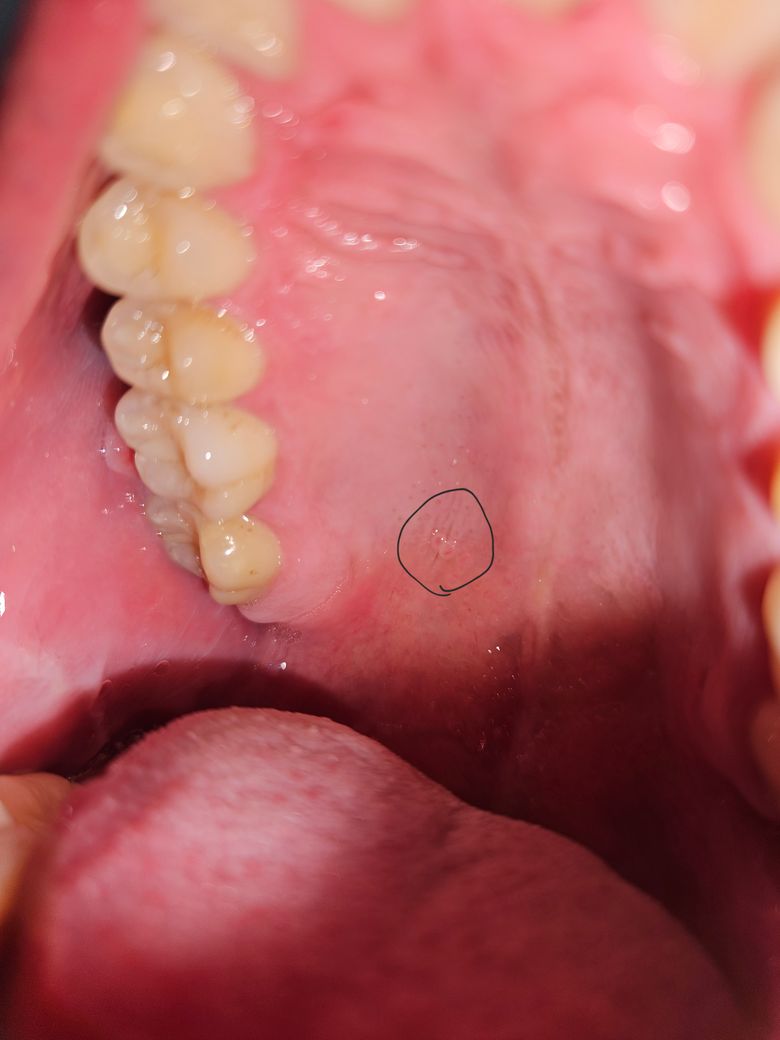

입천장 통증없는 동그란 돌기같은게 있는게 무엇인가요?

언제부터 생겼는지는 잘 모르겠는데, 전에도 비슷하게 있었던 것 같습니다. 최근에 또 우연히 혀로 만지다가 발견했습니다. 통증은 전혀 없고 불편함도 없는데 신경쓰이네요.

사진으로는 정확한 확인이 힘들어 보입니다. 점막 조직에 생긴 단순한 점액 중일 수 있고 치아 뿌리 쪽에 염증이 생긴 것일 수도 있습니다. 자세한 확인을 위해서는 치과에서 진료를 받아보는 것을 권유드립니다

입천장이 자극을 받아서 물집같은게 생긴거 같습니다. 시간이 지나면 자연스럽게 사라지니 너무 걱정하지마세요.

사진상으로 봤을때는 단순 구내염 내지는 구강 내 다형홍반(erthema multiforme) 으로 예상됩니다. 단순 구내염의 경우 보통 치료는 불필요하고 1~2주면 사라지는 증상입니다. 다형홍반의 경우 항바이러스제 약처치가 필요합니다.